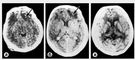

При компьютерной томографии в 1/3 наблюдений выявляются очаговые поражения мозга в виде неоднородного повышения плотности (рис. 1, а). Определяется чередование участков, имеющих повышенную (плотность свежих сгустков крови) и пониженную плотность (плотность отечной и/или размозженной ткани мозга). В наиболее тяжелых случаях деструкция вещества мозга распространяется в глубину, достигая подкорковых ядер и желудочковой системы. Наблюдение в динамике показывает постепенное уменьшение объема участков уплотнения, их слияние и превращение в более гомогенную массу уже на 8—10 сут. Объемный эффект патологического субстрата регрессирует медленнее, указывая на существование в очаге ушиба нерассосавшейся размозженной ткани и сгустков крови, которые к этому времени становятся равноплотными по отношению к окружающему отечному веществу мозга. Исчезновение объемного эффекта к 30—40 сут. после травмы свидетельствует о рассасывании патологического субстрата и формировании на его месте зон атрофии или кистозных полостей.

Примерно в половине наблюдений ушиба мозга тяжелой степени при компьютерной томографии выявляются значительные по размерам очаги интенсивного гомогенного повышения плотности с нечеткими границами (рис. 1, б), указывающие на значительное содержание в зоне травматического поражения мозга жидкой крови и ее сгустков. В динамике отмечается постепенное и одновременное уменьшение на протяжении 4—5 нед. размеров участка деструкции, его плотности и обусловленного им объемного эффекта.

При диффузном аксональном повреждении на компьютерных томограммах обнаруживается увеличение объема мозга (вследствие его отека и набухания), проявляющееся сужением или полным сдавлением боковых и третьего желудочков, субарахноидальных конвекситальных пространств и цистерн основания мозга. На этом фоне могут выявляться мелкоочаговые геморрагии в белом веществе полушарий мозга, мозолистом теле, а также в подкорковых и стволовых структурах (рис. 1, в).

Эпидуральная гематома на компьютерной томограмме имеет вид двояковыпуклой (рис. 2, а), реже плосковыпуклой зоны повышенной плотности, примыкающей к своду черепа. Гематома имеет ограниченный характер и, как правило, локализуется в пределах одной-двух долей. При венозных источниках кровотечения она может распространяться на значительном протяжении и иметь серповидную форму.

Для субдуральной гематомы на компьютерной томограмме чаще характерно наличие серповидной зоны измененной плотности (рис. 2, б) плосковыпуклой, двояковыпуклой или неправильной формы. Часто субдуральные гематомы распространяются на все полушарие или большую его часть. Внутримозговые гематомы имеют вид круглых или вытянутых зон гомогенного интенсивного повышения плотности с четкими границами (рис. 2, в). Гематомы формируются как вследствие прямого повреждения сосуда, так и при ангионекрозе в очаге размозжения мозга. Внутрижелудочковые гематомы выявляются зоной интенсивного гомогенного повышения плотности, по своей топике и форме соответствующей тому или иному желудочку мозга (рис. 2, г).